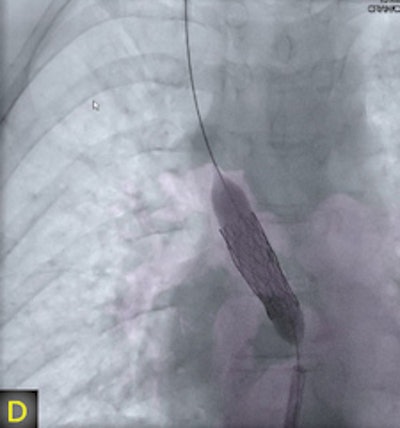

"The fusion of 3D reconstructions with live fluoroscopic images during catheterization may help to find the ideal fluoroscopic angulation during catheter-based interventions, to achieve difficult vascular crossings by the wire or the catheter, to choose the most appropriate material for catheterization, and to define and control optimized positioning of implants such as stents or valve prostheses," Glöckler and colleagues explained.

"One unique feature of FD-CT is the possibility of merging 3D reconstructions with the real-time fluoroscopic image," a potentially useful way to identify ideal C-arm angulations for achieving wire passage for atypical vascular crossings, and to optimally depict the implant position of coils, plugs, stents, and valves," Glöckler and colleagues wrote. "In fact, image fusion of 3D reconstructed FD-CT images with the live fluoroscopic image was frequently rated as 'very useful' (57.4%)."

A typical example is the visualization of the coronary arteries during transcatheter pulmonary valve implantation.